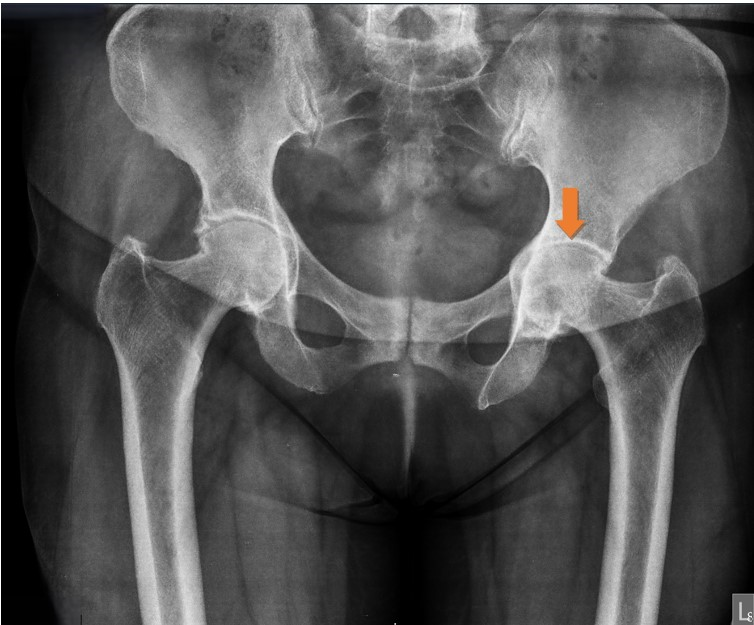

Press-fit type THA was performed on a 57-year-old patient who suffered from chronic symptoms of hip osteoarthritis (Fig. 1 and 2).

Figure 1: Pre-operative pelvis X-ray, anteroposterior view. Moderate left hip joint arthritis.